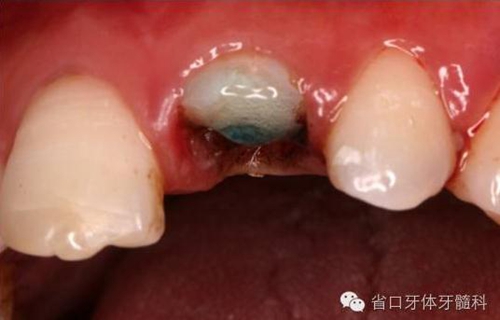

圖4. 拔除斷冠后的唇面照片

圖5. 拔除斷冠后的發(fā)現(xiàn)腭側(cè)斷面及齦下約3毫米

圖8. 21/行根管治療術(shù),保留根尖約5mm的根充物,根中上段預(yù)留空間以預(yù)備纖維樁道。

圖9. 腭側(cè)電刀切齦止血、暴露斷面,殘根斷面磷酸酸蝕

圖10. 11. 斷冠磷酸酸蝕處理

圖12. 超聲蕩洗纖維樁道

圖13. 纖維樁及斷冠粘接固定